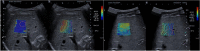

Methods: In 90 consecutive pediatric patients, standardized 2D-SWE was performed during general anesthesia and free breathing. Liver stiffness was estimated with SWE followed by a percutaneous biopsy from the corresponding area. SWE values were compared with histology with fibrosis scored according to Batts & Ludwig classification (grade 0-4 = F0-F4) and to hepatic biomarkers.

Results: Four patients with SWE interquartile range (IQR)/median ≥ 30% kPa were excluded. The remaining 86 children (59% males) had a mean age = 10.2 years (0.1-18). The distribution of individuals with median (min;max) SWE values (kPa) within each fibrosis grade were; F0[n = 10; 5.0(3.4;6.3)], F1[n = 24; 5.0(3.6;8.7)], F2[n = 32; 5.8(3.5;13.4)], F3[n = 12, 7.5(4.0;14.4)], and F4[n = 8; 12.5(6.6;21.0)]. There was a significant difference between fibrosis grades (0.03 > P < 0.002) except between F0 and F1 respectively between F1 and F2. The AuROC differentiating F0-1 from F2-4 was 0.77(95% CI: 0.67-0.87). A cutoff SWE value of ≤4.5 kPa yielded 90% sensitivity and 68% specificity to rule out significant fibrosis (F2-F4). Out of the 18 children (21%) with SWE value ≤4.5 kPa, 12 had grade F0-1 and 6 had F2, although including some confounders for increased SWE measurements as steatosis/hepatitis/cholestasis.